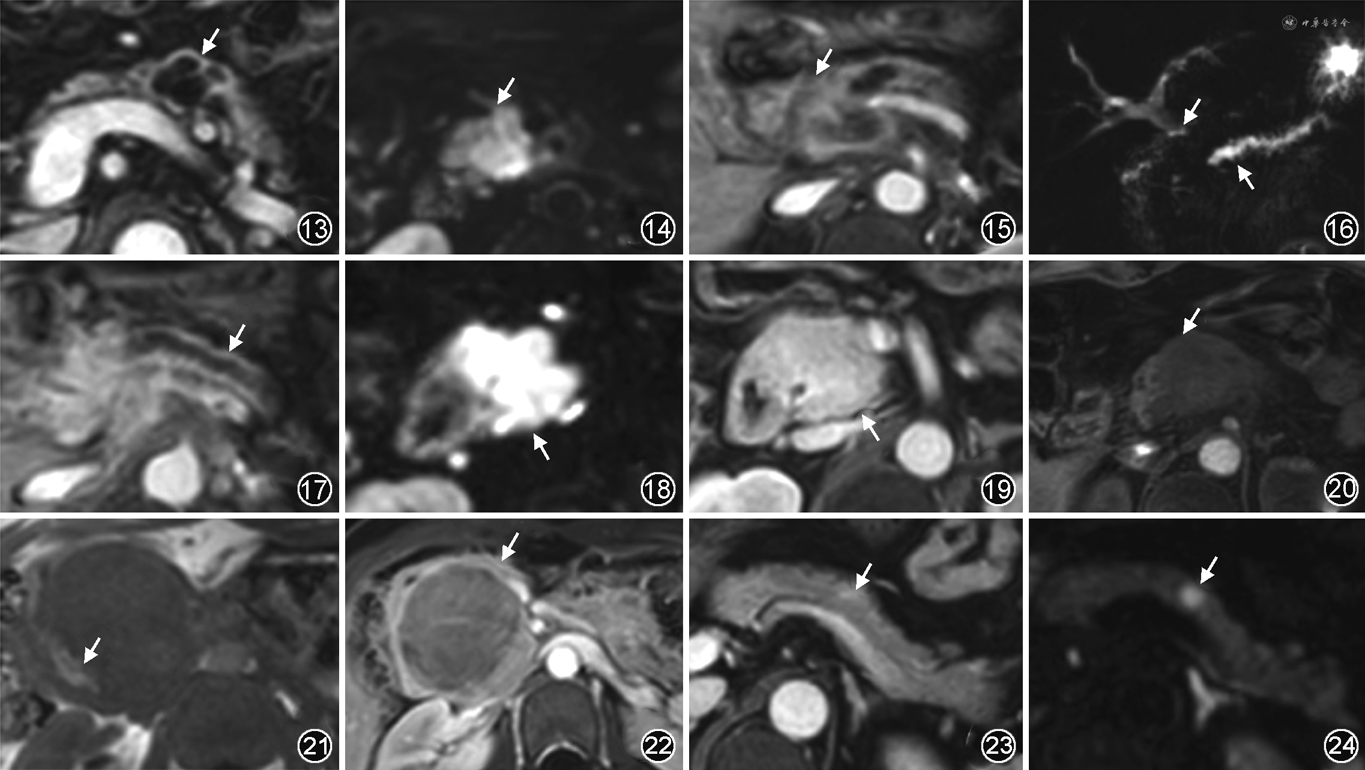

MRI影像特征:典型的SCN多发生在胰腺体尾部,可分为微囊型、巨囊型(或寡囊型)、遗传性肿瘤综合征(von-Hippel Lindau,VHL)相关的浆液性囊腺瘤和混合型。微囊型SCN最常见,表现为边界清晰、分叶状肿块,通常为2~16 cm,囊腔小,数目多,一般>6个,单个微囊为1~20 mm,具有典型的蜂窝状外观[10]。在20%微囊非常小的病例中,T2WI和MRCP可以帮助诊断CT无法辨别的微囊成分,避免误诊为实性肿物(图1,2)。巨囊型和混合型SCN不太常见,多发生在年轻人群中。混合型SCN中的微囊常位于中心部位,大囊围绕在周围。囊性成分通常表现为T2WI高信号(图3),而T1WI的信号强度则根据浆液内出血的量而改变[7]。由于SCN分隔间有血管成分,增强扫描囊壁和分隔可呈轻度强化(图2,4)。约33%的SCN中可见特异性的星状纤维性瘢痕,部分钙化,在T1WI和T2WI上呈低信号[11],中心瘢痕及分隔在门静脉期及延迟期持续强化。SCN与胰腺导管不相通,这是区分SCN和IPMN的一个重要特征,肿块较大时可能会压迫胰管[7]。VHL相关的SCN多见于年轻女性,大部分无临床症状,部分可见压迫症状,表现为多发囊性肿瘤,偶尔也会与pNET或PDAC共存[9]。罕见情况下,SCN出现远处转移,则诊断为浆液性囊腺癌。

MRI影像特征:BD-IPMN仅累及分支胰管,最常位于钩突,其次胰尾部[13]。典型的BD-IPMN可表现为单个大囊性病灶(图5),囊内可包含或不包含分隔[1]。BD-IPMN也可以表现为多发小囊性病灶,形似葡萄(图6)。MD-IPMN可累及部分或整个主胰管,约2/3的MD-IPMN累及主胰管近端(胰头区),在脂肪抑制T2WI上,主胰管全程扩张或呈节段性扩张,呈明显高信号[13]。仅少部分MD-IPMN导管内可见乳头状赘生物,在T2WI上呈低信号,明显附着在管壁上(图7),增强扫描可见强化(图8)。因扩散受限,MD-IPMN在DWI上呈高信号,ADC图上呈低信号。MRCP可清晰地显示胰腺囊性灶与胰管相通(图9),这是IPMN的特异性征象。MD-IPMN引起的导管扩张会逐渐变细,没有局灶过渡点,而慢性胰腺炎则会出现局灶狭窄[7]。随着病程发展,胰腺实质可逐渐萎缩,此时需要与PDAC相鉴别。混合型IPMN兼有上述两型的特点[13]。

根据2017版国际共识指南,发生在胰头的IPMN导致梗阻性黄疸、强化壁结节≥5 mm、主胰管内径≥10 mm是IPMN恶变的高危征象(图10),间隔增厚或增强时也要怀疑恶变的可能[14, 15]。伴浸润癌的IPMN需要与ITPN鉴别,IPMN虽然伴有实性成分,但因胰管内富含黏液,整体仍以囊性成分为主。

MRI影像特征:根据累及胰管部位,ITPN可分为主胰管型(约占95%)、分支胰管型和混合胰管型。根据病灶形态分为肿块型和管腔型[16]。ITPN可发生在胰腺任何部位,呈分叶状,边界清楚,平均直径约6 cm,部分肿块型ITPN体积较大并突破胰腺轮廓,但病灶仍局限于胰管内。管腔型ITPN肿瘤体积较小,未突破胰腺轮廓,局限于胰管内或充满胰管。ITPN在T1WI上表现为不同程度的低信号,在T2WI上呈不同程度的高信号。“双色征”和“酒瓶塞征”是ITPN的典型影像学特征。“双色征”代表扩张主胰管内的肿瘤和胰液分别呈两种不同的信号(颜色),在T1WI上肿瘤呈等或低信号、胰液呈低信号,在T2WI上肿瘤呈等或高信号、胰液呈明显高信号(图11)。“酒瓶塞征”指肿瘤局限或填充在胰管内,被扩张胰管内的胰液包围,胰液为“酒瓶壁”、肿瘤为“瓶塞”。增强扫描ITPN呈较均匀的轻度强化。当ITPN发生在胰头时,可侵犯胆总管下端,引起胆总管、肝内胆管扩张、胰腺实质萎缩,需要与PDAC鉴别,ITPN局限或填充在胰管内,呈“酒瓶塞征”,而PDAC可突破胰管及胰腺轮廓向外浸润;且ITPN信号比PDAC均匀[16]。病变沿胆总管继续向下进展,可侵犯十二指肠,此时需与壶腹周围癌相鉴别。

MRI影像特征:超过95%的病变发生于胰腺体尾部,通常较大,文献报道的平均直径为6~11 cm[13]。典型表现为大的圆形或卵圆形肿块,最常表现为单囊(80%),如果出现分隔,一般较SCN少,且通常位于肿瘤的外围(图12)。囊液表现为T2WI高信号,T1WI一般为低信号,当囊内有出血或蛋白成分较多时,可呈高信号。大多数MCN是良性的,囊壁光滑,分隔或壁较薄,增强扫描囊壁和分隔呈中等强化(图13)。少数MCN可伴有胰腺导管扩张,需要与BD-IPMN鉴别,MCN的囊腔与胰管不相通,而BD-IPMN与胰管相通,MRCP序列可以清晰地观察到病灶是否与胰管相通[7]。当MCN出现囊壁不规则增厚、实体成分强化、壁结节、乳头状突起、直径>4 cm、患者年龄大于55岁或病灶周围出现蛋壳样钙化时,应怀疑恶变的可能。DWI对壁结节、囊壁增厚显示较为敏感,可以帮助早期识别[4]。